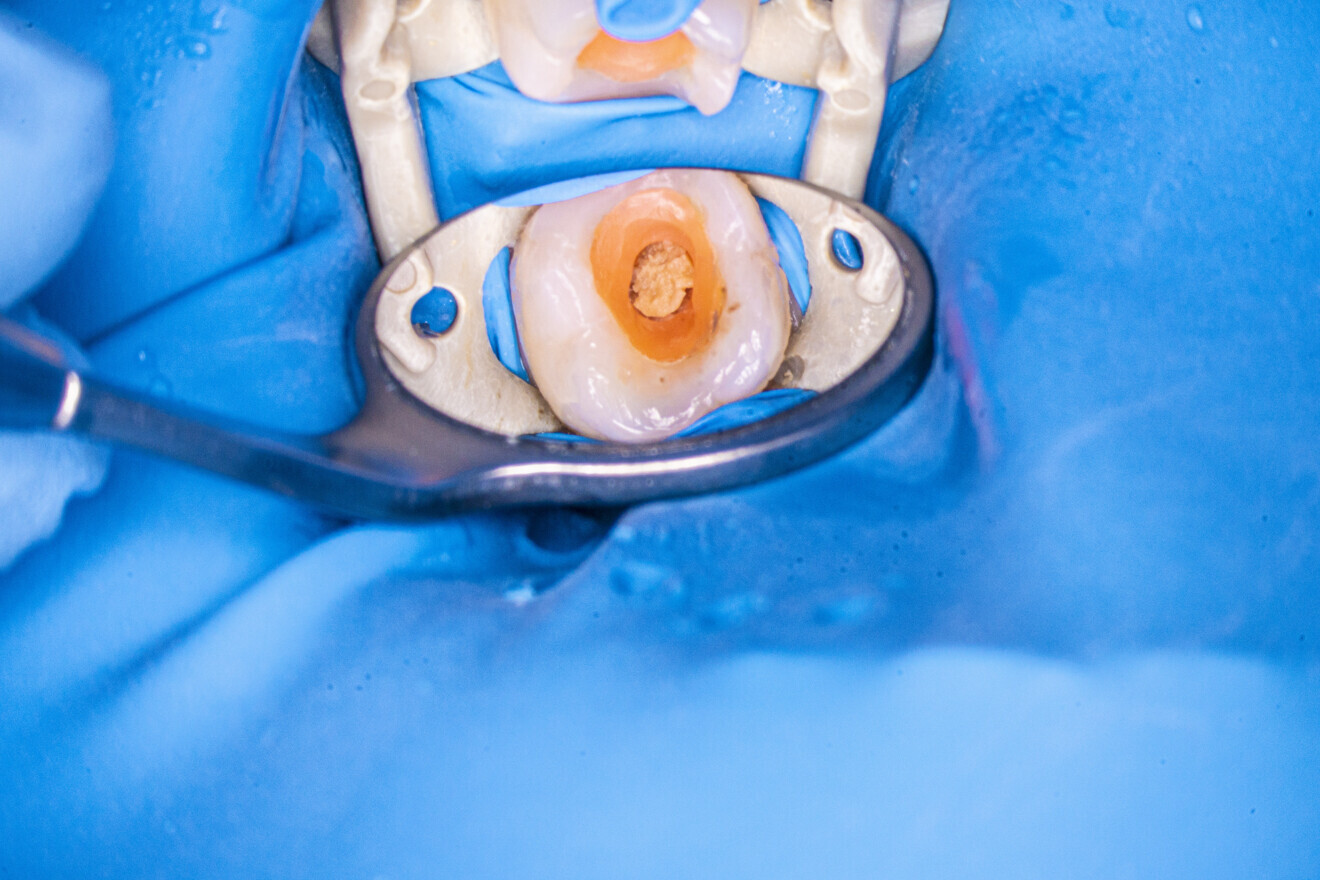

Fig. 29: Tooth after removal of the caries and sealing of the chamber with flowable composite and dental dam.

The patient was referred to the office for root canal retreatment of three teeth before prosthodontic treatment. One of these teeth was the mandibular left first molar. The CBCT scan revealed two radiolucent spaces around both roots (Fig. 26). Moreover, the periapical radiograph showed a broken file in the mesiobuccal canal (Fig. 27). After administering anaesthesia and placing a dental dam, the old restorations were removed, a temporary composite build-up was performed, and the tooth was sealed with flowable dental dam (Figs. 28 & 29). The old gutta-percha cones were removed from all the canals (Fig. 30).

After the removal of the gutta-percha and cleaning of the root canals, it was apparent that a large amount of the dentine had been removed from the orifice of the mesiobuccal canal (Fig. 31). Most probably, this had occurred during an attempt at removing the broken file in the previous treatment. Fortunately, there were no visible signs of perforation in the orifice. The damaged wall was sealed with composite resin (Fig. 32). Irrigation of the mesiobuccal canal with the AutoSWEEPS mode and sodium hypochlorite and inspection under 16× magnification revealed two pieces of the broken instruments (Fig. 33), complicating treatment. The tips of both files were visible, but both were also jammed. An attempt at removal with an ultrasonic file was ineffective, so the flat SWEEPS 300/20 fibre tip was used with the AutoSWEEPS mode at a power of 1.2 W. After a few minutes of irrigation with sodium hypochlorite and EDTA, both file pieces started to move a little, indicating that both were removable. Both pieces were retrieved with a lasso loop tool (BTR Pen, CERKAMED; Fig. 34). A periapical radiograph was performed to confirm that there were no more broken file pieces (Fig. 35).